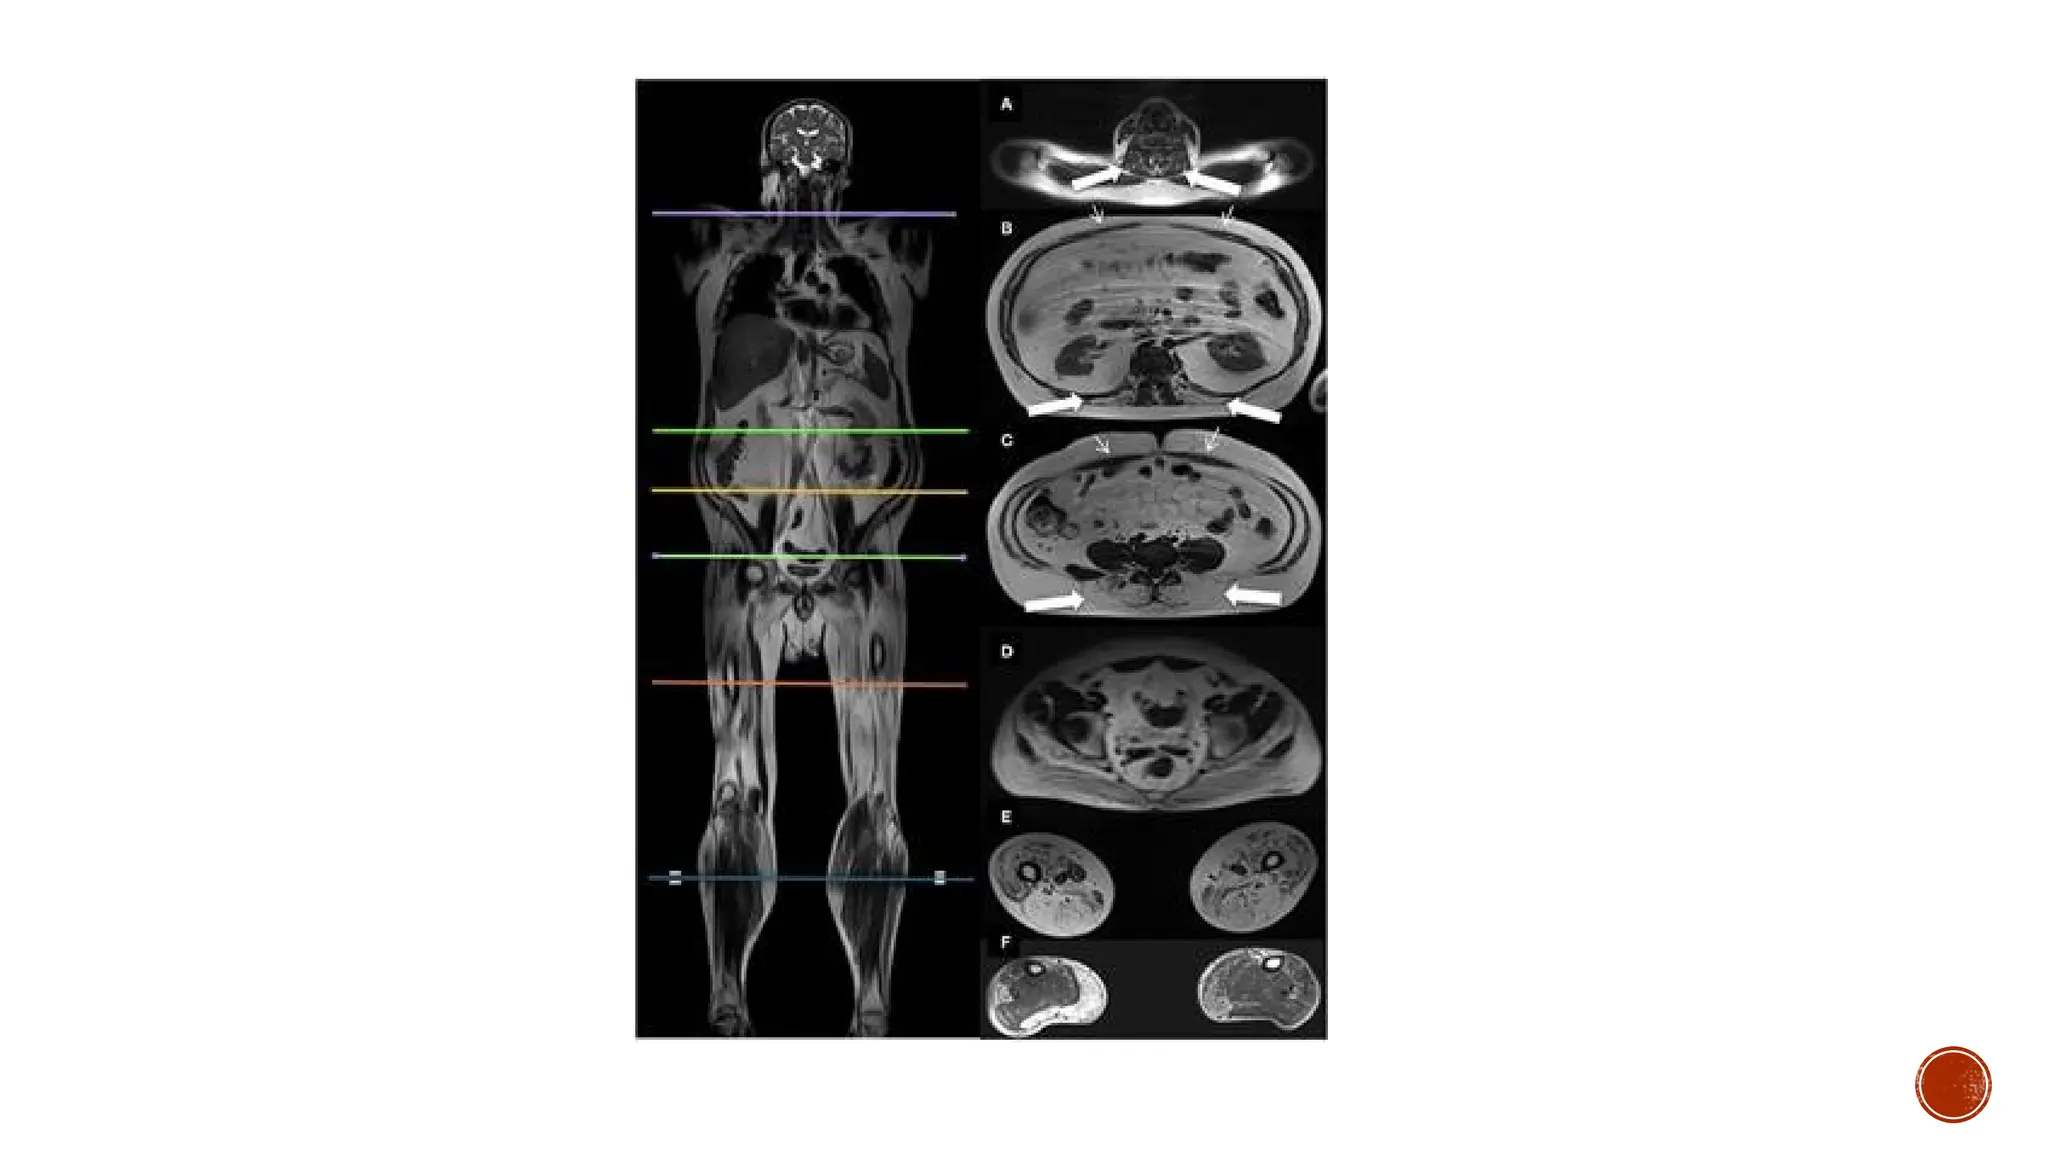

X RAY VIEW OF DUCHENNE MD

X RAY VIEWOF DUCHENNE MD